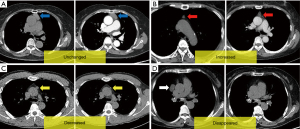

Collected data included patient demographics, initial CT and MRI findings, lesion size at initial and follow-up imaging, follow-up duration, and surgical history. Lesion size was defined as the longest axial dimension measured on CT. Significant size changes (increased or decreased) were defined as a variation of ≥10% from the initial size, excluding differences of ≤1 mm. Although there is no clear definition of significant cyst growth, we referred to a criterion for pancreatic cysts, wherein a 20% increase in the long-axis diameter was considered meaningful for lesions ≥1.5 cm (7). Lesions were categorized into four groups based on size changes: unchanged, increased, decreased, or disappeared (Figure 2).

Patients were classified into four groups based on cyst size changes: unchanged, increased, decreased, or disappeared (Table 3).

During the follow-up period, 162 of 194 patients (83.5%) showed no significant change in thymic cyst size (unchanged group). Of these, 94 (58.0%) were male, closely reflecting the overall sex ratio of the cohort. The mean follow-up period was 1.74 years [interquartile range (IQR), 0.64–2.73 years].

Thirteen patients (6.7%, eight females) showed a decrease in cyst size (decreased group) and five patients (2.6%, three females) showed complete cyst disappearance or reduction to a size too small to be evaluated (disappeared group). These patients represent 9.3% of the entire cohort, and had relatively high proportions of females (61.5% and 60.0%, respectively). The mean follow-up durations were 1.94 and 1.40 years, respectively.

Fourteen patients (7.2%) showed an increase in cyst size (increased group), with the highest proportion of females (71.4%) among the four categories. The mean follow-up period in this group (3.12 years) was relatively longer than the other groups, with a wide distribution (IQR, 1.04–4.67 years), indicating greater variability compared to other groups.

Increased group: the initial mean cyst size was 25.7 mm (IQR, 11.0–39.8 mm, SD: 16.6 mm). At final follow-up, the mean cyst size increased to 31.8 mm (IQR, 18.0–50.8 mm, SD: 22.8 mm). The mean size increase was 8.9 mm (IQR, 5.0–9.0 mm), with most cysts enlarging by <1 cm over the 3.12-year follow-up. Notably, no cases exhibited features indicative of malignancy, such as an increase in the solid component, wall thickening, enhancement, or septation.

Each group exhibited distinct patterns of cyst size change, with the majority showing minimal to no significant changes over time. Those with increased or decreased size tended to show broader variability in cyst dimensions.